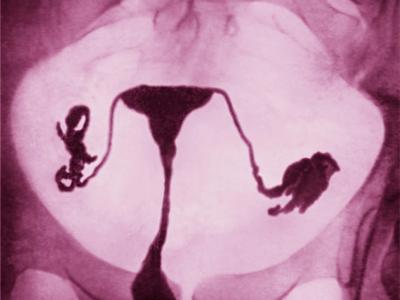

这张色彩增强子宫输卵管摄影显示女性生殖系统,包含输卵管和健康的子宫。PHOTOGRAP...